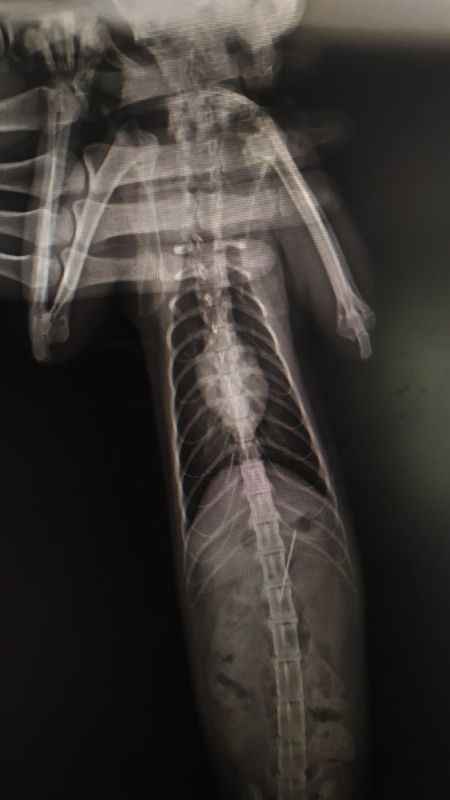

Kedinin midesinden dikiş iğnesi çıktıBolu’da rahatsızlanarak veteriner hekime götürülen yaramaz kedinin midesinden, yuttuğu dikiş iğnesi çıktı.

Bolu’da kedisinin rahatsızlandığını fark eden bir kişi veteriner hekime başvurdu. Edinilen bilgiye göre, özel bir veteriner kliniğinde muayene edilen kedinin röntgeni çekildi. Kedinin midesinde dikiş iğnesi olduğu görüldü.

Endoskopiyle dikiş iğnesi kedinin midesinden çıkartıldı. Bir süre veteriner kliniğinde müşahede altında tutulan kedi taburcu edildi.

Kedinin dikiş iğnesin yuttuğu öne sürüldü.